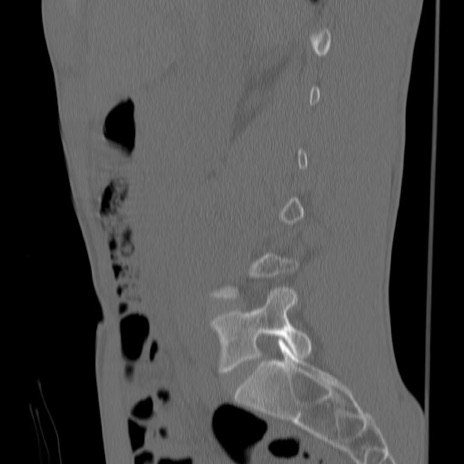

症例3 腰椎CT(矢状断像)

【症例】30歳代男性

【主訴】腰痛

【現病歴】本日旅行先で観光中に、友人と衝突し転倒し受傷。

【身体所見】麻痺なし、右下腿内側前面外側、左下腿内側に知覚鈍麻・しびれ

異常所見と診断は?

腰椎CT